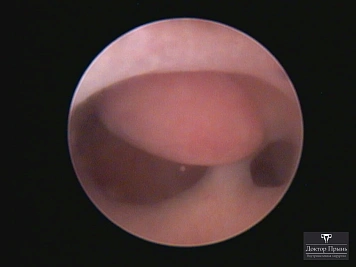

Фотогалерея

Синехии, рассечённые Прынь Д.В.